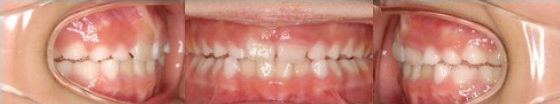

Pre-Ortho type 2. 개방교합 전용

9세남아, 프리올소 착용 6개월 후

다음, 개방교합 교정전용 타입입니다.

개방교합은 어금니를 맞물려도 앞니는 떠있는

상태를 유지하게 되는데요. 이 타입을 착용하여

양호한 교합으로 유도하게 됩니다.